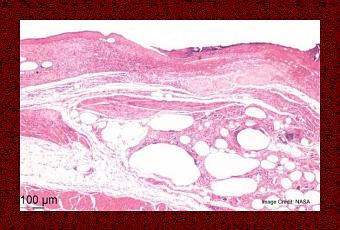

Ce dispositif électroactif qui se présente sous forme d’échafaudage de fluorure de polyvinylidène (PVDF) est appliqué directement sur le site de la plaie.

Source: NASA Nov, 2016 Electroactive Material for Wound Healing (Visuel@NASA)